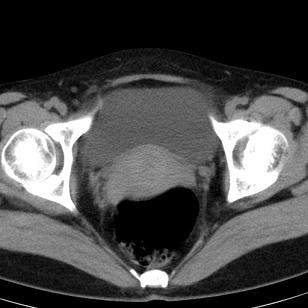

标题: CT19559:子宫及附件正常吗?

女,35岁,反复下腹部隐痛数月。

感觉上,子宫好象大了点

如果未孕,子宫体稍大,宫腔增宽,附件区未见异常密度影,还是建议结合b超检查为好,ct平扫对妇科没有优势。

子宫弥漫性等密度肿大,宫腔内缘见结节影突入腔内,子宫内膜异位可能